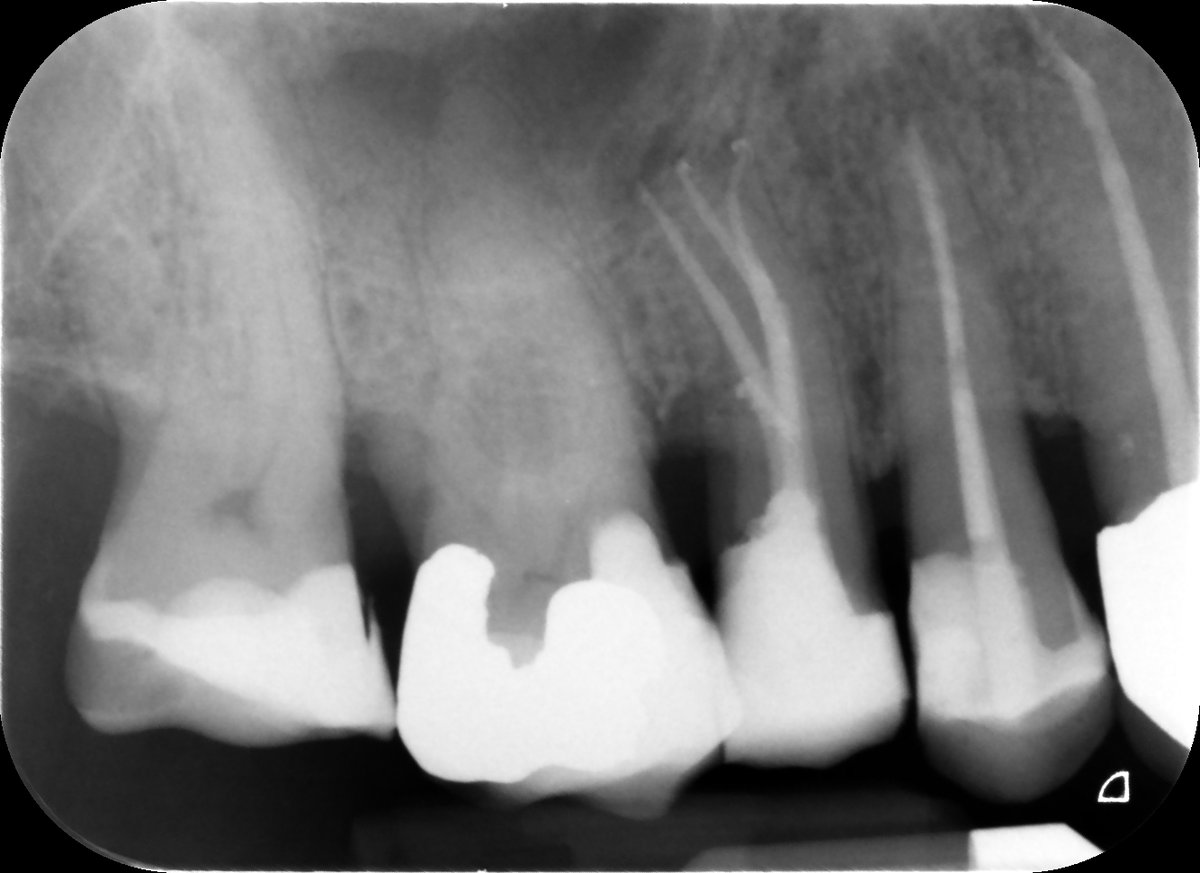

2-visit reRCT UR6 - insane apical delta anatomy P and MB canals - all thanks to the power of hypochlorite!🤣 Edge Endo preps VC obturation #savingteeth #endodontics

2-visit reRCT UR6 - insane apical delta anatomy P and MB canals - all thanks to the power of hypochlorite!🤣

Edge Endo preps VC obturation #savingteeth #endodontics